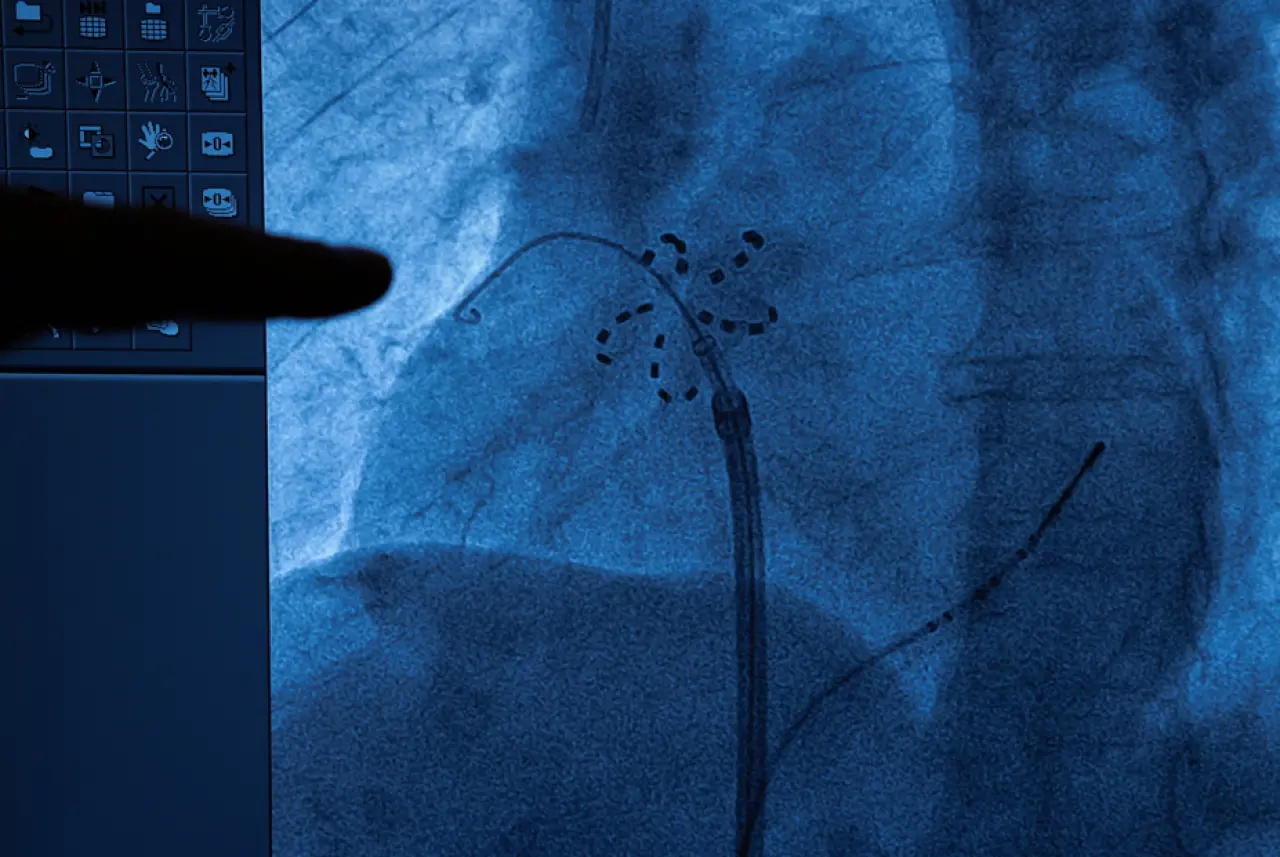

Kasıktan girilerek damar yoluyla kalbe yönlendirilen özel bir kateter aracılığıyla uygulanan bu yöntem, çevre dokulara zarar vermeden problemli bölgeyi saniyeler içinde etkisiz hale getiriyor.